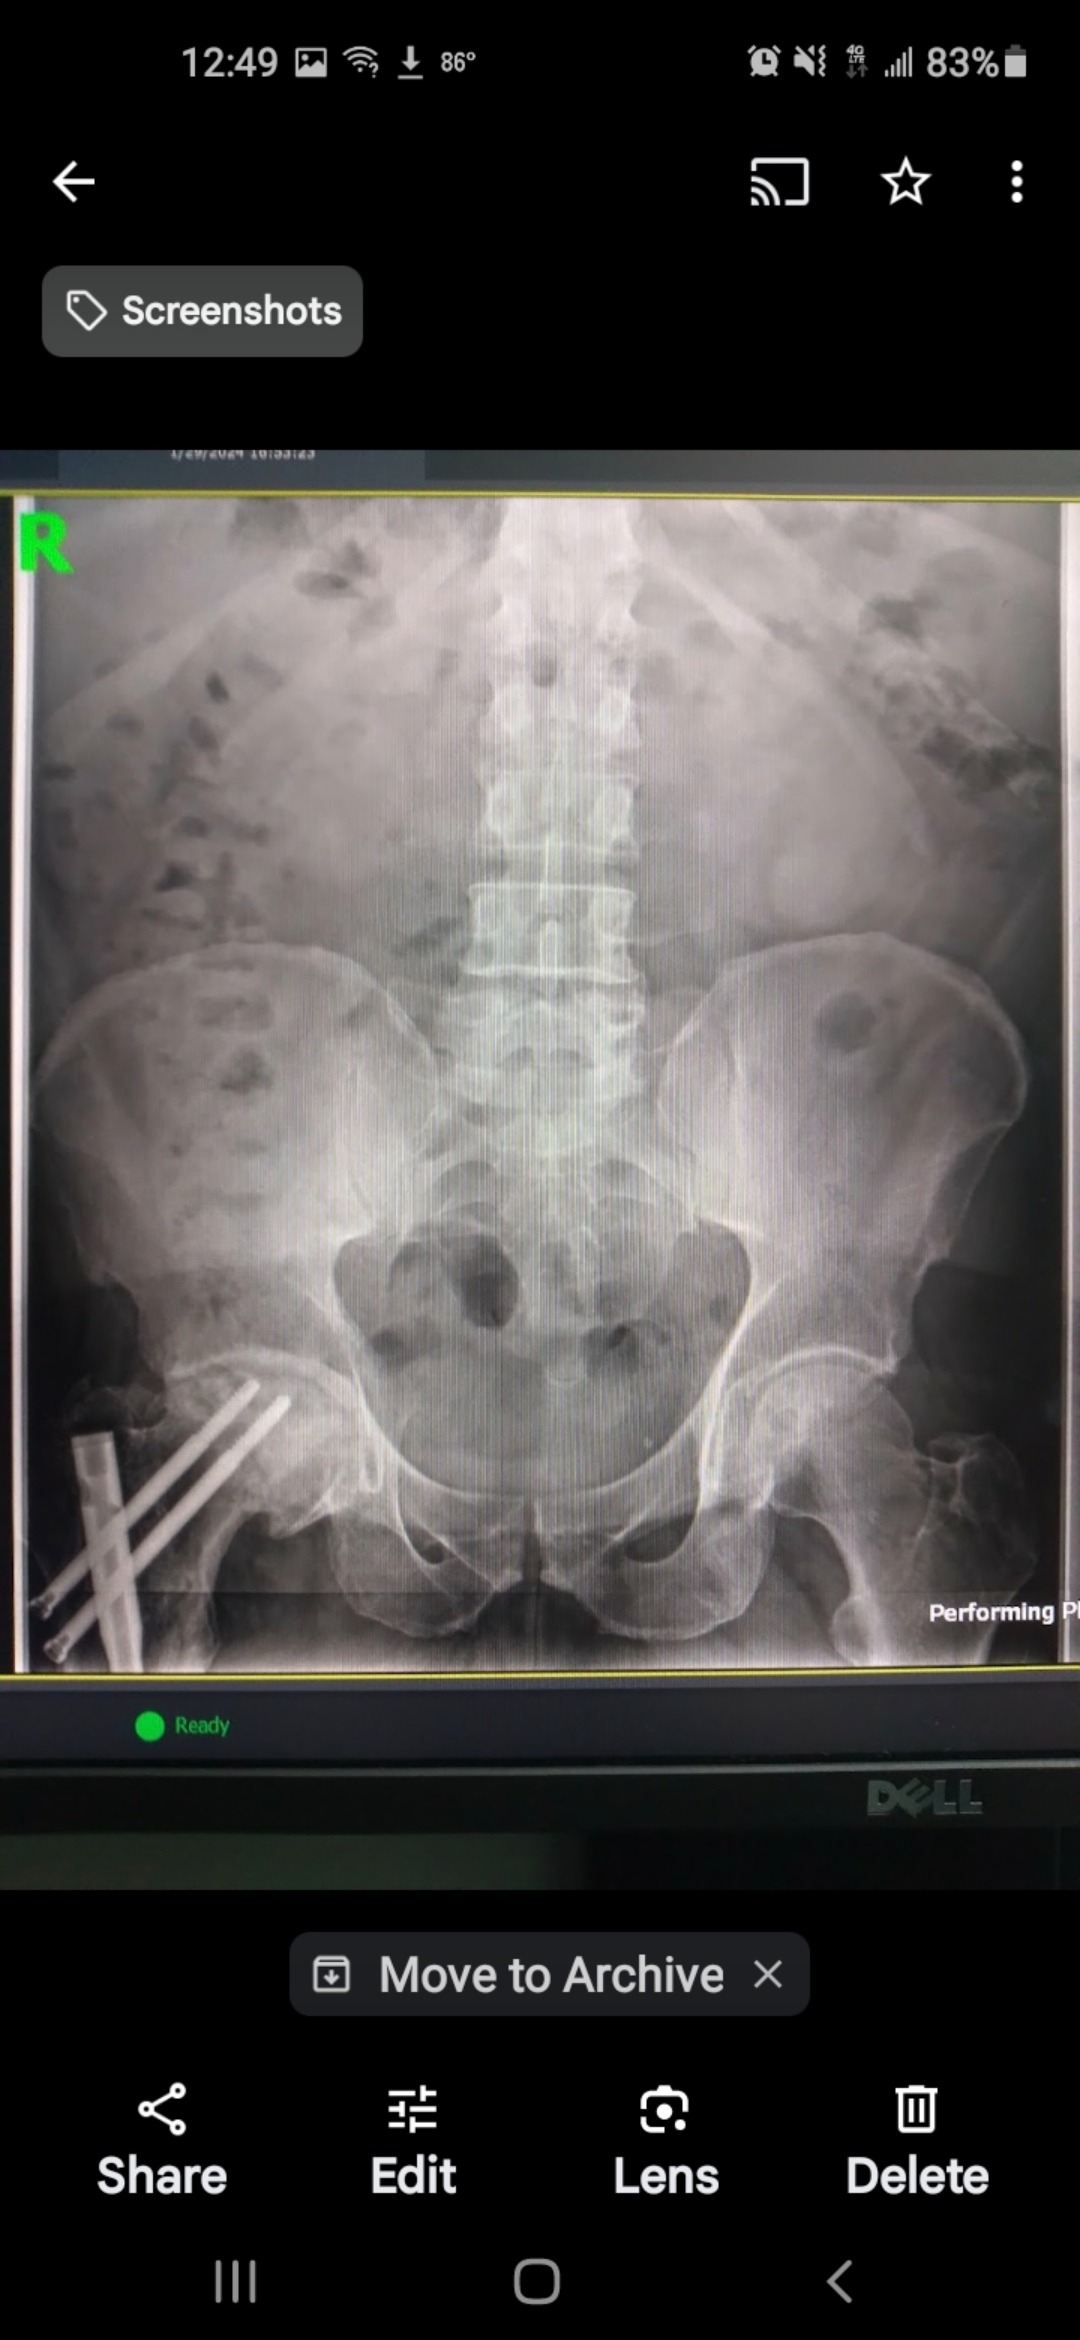

Our dear friend Oliver is facing a major surgery to replace his hip. Anyone who knows Oliver knows just how much he gives to our recovery community — offering support, encouragement, and a listening ear to so many of us on our journeys. Now, it’s our turn to show up for him.

Oliver has already been unable to work since March due to his condition. This has made his financial need even greater, but those who know him also know it’s worth helping him gain the quality of life he deserves — especially after all he has done for others.